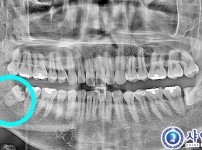

완전매복사랑니발치 - 구강외과전문의

해당 게시물은 의료법 제56조에 의거하여 로그인 후 열람이 가능합니다.

복잡매복사랑니발치 - 구강외과전문의